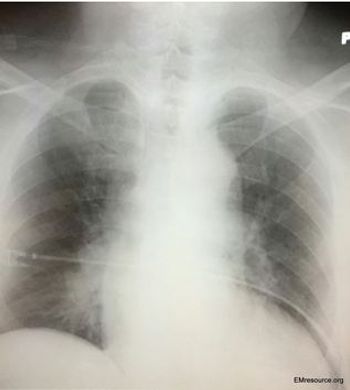

The patient with hypertension and syncope had cardiac tamponade. Causes, symptoms, and treatment described here.

A man with a history of hypertension had syncope and felt “sweaty.” Chest x-ray was normal. What’s your next test?